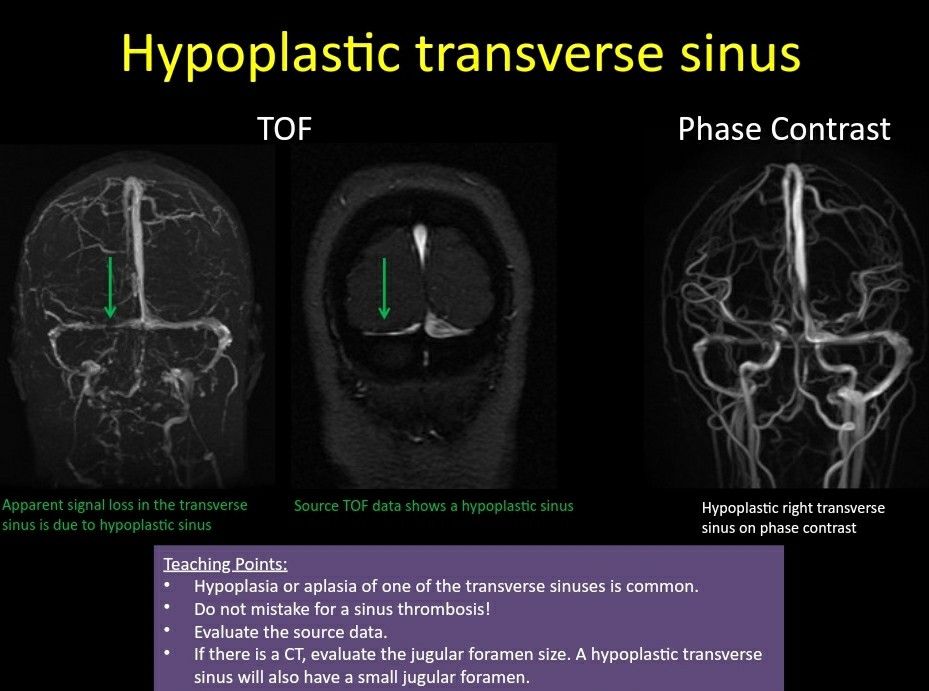

Unlike Transverse Sinus Thrombosis That Will Display An Abnormal Signal In T1 T2 Images While Flow Void Remains In A Hypoplas Sinusitis Thrombosis Radiology